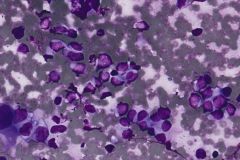

Specimen Type: FNA of Station 7 Lymph node, Diff-Quik and Papanicolaou Stained smears, ThinPrep® Non-Gyn cytology, Formalin-Fixed Cell Block

Cytologic Diagnosis: Positive for Malignant Cells, Metastatic Carcinoma of Breast Origin. The malignant cells are positive for GATA3, AE1/AE3 and estrogen receptor. P40, TTF-1 and Napsin A are negative.

Ductal breast carcinoma specimens are highly cellular and consist of a variety of cell arrangements. The cells will commonly be seen as poorly cohesive clusters, some isolated single cells, and rare sheets of cells. These specimens will have enlarged and hyperchromatic nuclei that are eccentrically placed and often protruding from the cytoplasm. The chromatin has a bland appearance, ranging from finely to coarsely granular, with prominent, irregularly shaped nucleoli. Myoepithelial cells sitting on top of or lining the ductal breast cells are helpful in determining if the specimen is benign and should not be present in IDC specimens. The background of IDC is usually clean, but inflammation, blood, and granular debris may be observed.1,14 Immunohistochemistry (IHC) markers that can be used to stain for ductal breast carcinoma are Ki-67, p63, CK5/6, ER, Mammaglobin, GCDFP-15, E-Cadherin and GATA3. Double staining for cytokeratin, smooth muscle myosin heavy chain, Calponin, and/or p63 is helpful for determining if myoepithelial cells are present in the specimen.1,15 In the current case study, the patient’s specimen presented with marked cellularity consisting of a population of both 3-dimensional clusters of cells and many dyshesive single cells. In the smaller 3-dimensional clusters, some of the cells can be seen forming glandular structures and some look as if they are molded together. The nuclei are enlarged, eccentrically placed, and have a mix of both smooth and irregular nuclear contours. The cells all have high N/C ratios and there is a moderate amount of anisonucleosis. The chromatin has a predominantly hyperchromatic appearance, is finely granular and large prominent nucleoli can be observed. The cytoplasm is scant, has well-defined cytoplasmic borders, and is finely vacuolated. Mucinous vacuoles in the cytoplasm can be seen in the larger 3-dimensional clusters of cells. Crush artifact and necrosis can be observed in the background.